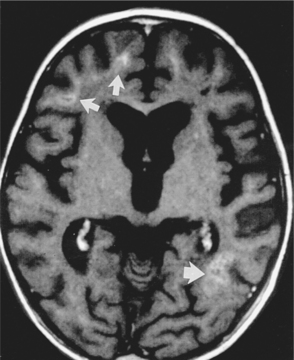

Pathogenesis.: The pathophysiologic basis for development of these tumors is unclear, particularly in immunocompetent patients. PCNSL most commonly originates from B lymphocytes and is associated with cytokines. In immunosuppressed patients it is almost always associated with latent infection of neoplastic B cells by Epstein-Barr virus. B cells infected with Epstein-Barr virus are immortalized and able to replicate spontaneously.58 The lymphoma cells typically assume a periventricular pattern, involving the deep white matter, basal ganglia, corpus callosum, and thalamus. PCNSL may also involve the CSF, the eyes, or the spinal cord. A large percentage of PCNSLs begin as solitary cerebral lesions but eventually develop into multiple lesions. Lesions in immunocompetent patients more often may be a single brain lesion, in a supratentorial location, and with frontoparietal lobe involvement. The diagnostic procedure of choice is a stereotactic (x-ray guided) biopsy, because patients derive no clinical benefit from surgical resection.58

Clinical Manifestations.: Symptoms and signs generally evolve over several months, including personality and behavioral changes, confusion, generalized seizures, and symptoms associated with increased ICP (headaches, nausea and vomiting). The most frequent presenting symptom in 30% to 40% of patients is impaired cognition.32 Focal neurologic signs such as hemiparesis or blurred or double vision may occur. The appearance on MRI or CT of multiple deep cerebral and periventricular lesions, along with an immunodeficient state, contributes to the diagnosis.65 Differential diagnosis includes infections, other tumors, and inflammatory disorders.